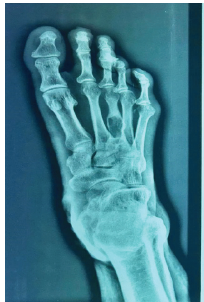

An Unusual Presentation of Keratinous Cyst – A Case Report

V Ashwanth , R V Raghav , Harish Kiran , Arjun Ganesh , Pravin K Vanchi , M Mohan Kumar

………………………………p.145-149